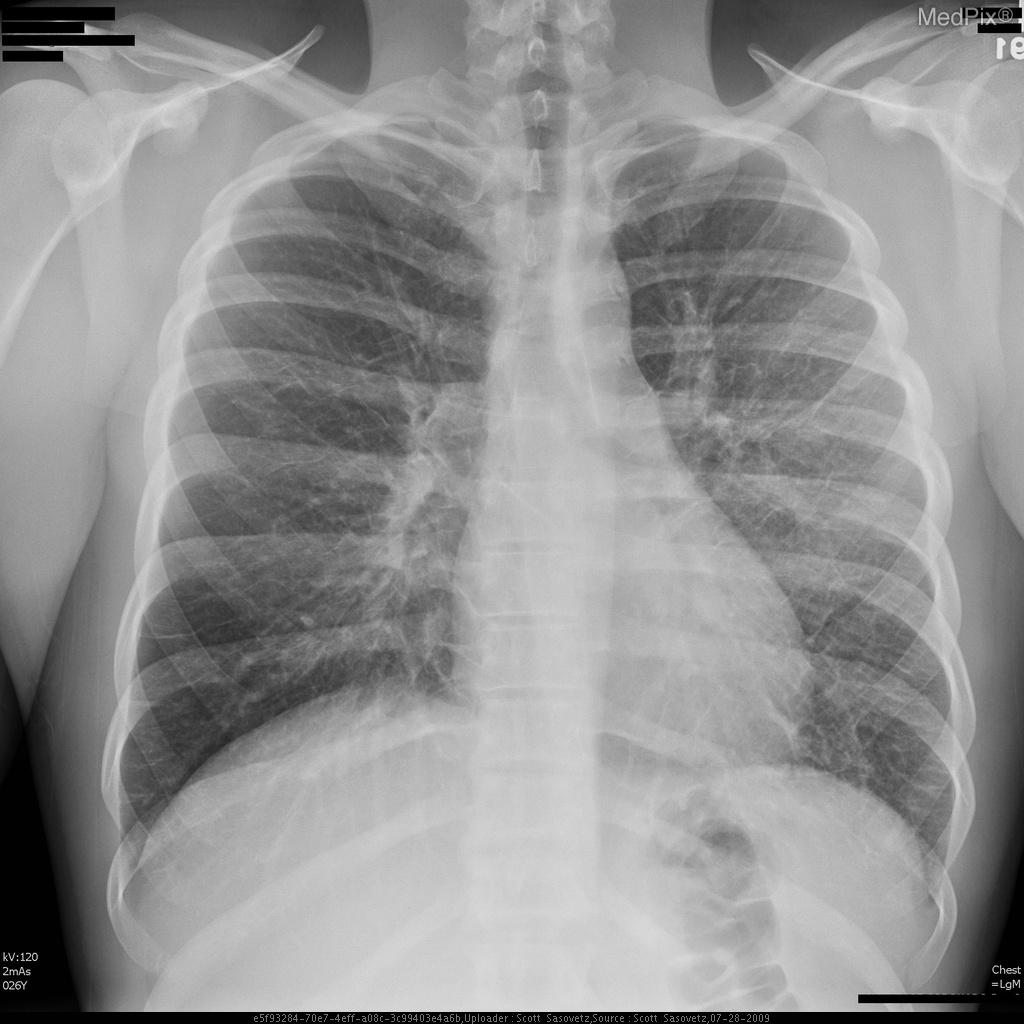

- Adequate inspiratory chest X-ray with clear visualization of both lungs, mediastinum, and diaphragm.

- Cardiac silhouette is normal in size; cardiac apex lies image-right (patient-left), consistent with expected anatomy.

- Pulmonary vasculature appears mildly prominent centrally, with increased perihilar markings suggestive of vascular congestion.

- Subtle hazy ground-glass type opacities noted in the perihilar regions, extending outward in a symmetric pattern (more conspicuous centrally than at the periphery).

- No focal lobar consolidation, no pleural effusion, and no pneumothorax identified.

- Costophrenic angles appear sharp bilaterally.

- Bony thorax visualized without acute abnormality.

Findings are most consistent with pulmonary edema. The hazy bilateral perihilar opacities and vascular congestion suggest an interstitial/alveolar fluid process consistent with pulmonary edema rather than focal pneumonia or chronic interstitial disease. The absence of cardiomegaly makes non-cardiogenic causes more likely (such as swimming-induced pulmonary edema). Context consistency: Consistent — the described clinical context (young swimmer with acute onset) aligns well with non-cardiogenic pulmonary edema findings. Confidence: 80%.